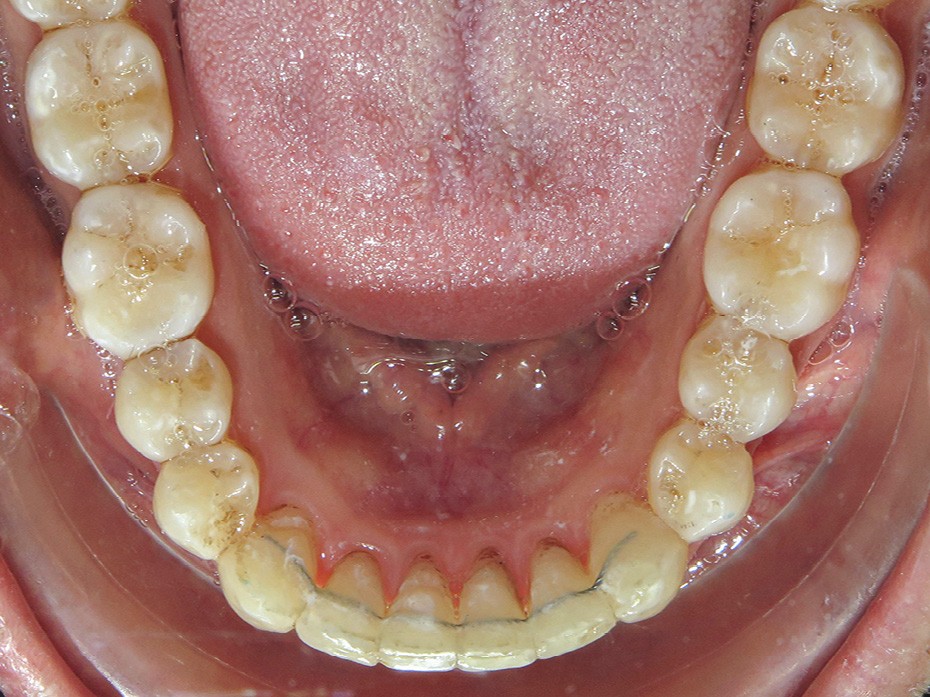

- réalisation d’une gouttière mandibulaire rigide englobant l’ensemble des dents mandibulaires. Cette gouttière a pour but de relier l’ensemble des dents de l’arcade inférieure (ancrage) et d’obtenir une désocclusion.

- collage de boutons sur les 13 et 23 (en composite pour améliorer l’esthétique) et de boutons métalliques (pour le confort) sur les 36 46

- port d’élastiques (3/16 4,5 Oz) reliant les boutons maxillaires à ceux mandibulaires pour obtenir une force de recul sur l’arcade supérieure et d’avancée sur l’arcade opposée (les mouvements ont été facilités par les extractions des 18 28). Les prémolaires n’étant pas collées, le mouvement généré est un mouvement de version et donc de redressement (car tipées au départ). Il est à noter que les boutons canins sont collés le plus cervicalement possible pour avoir une traction oblique avec les élastiques inter-arcades, afin d’avoir un mouvement de descente des canines supérieures qui sont trop hautes. L’intérêt d’avoir une gouttière mandibulaire par rapport à un arc lingual ou un dispositif multi-attaches, c’est qu’une gouttière contrôle mieux les mouvements de vestibulo-version des incisives mandibulaires induits par les élastiques.